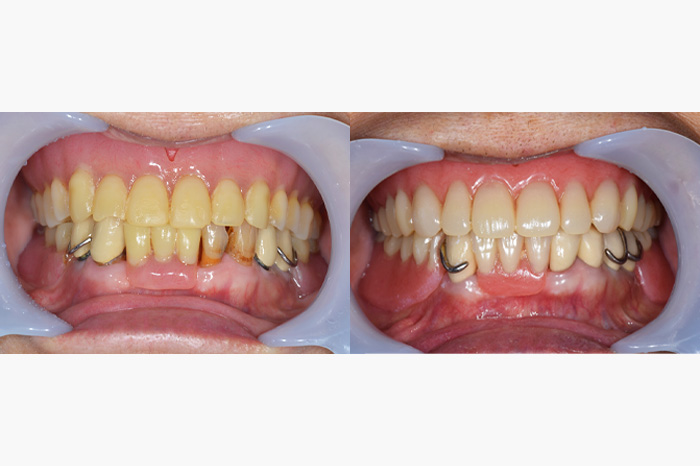

| 年齢 | 症例2 40代・女性 |

|---|---|

| 主訴 | 前歯を10年以上前に入れたが色が気になるので、変えたい |

| 治療内容 | 上顎右側犬歯から上顎左側犬歯までの6本のメタルボンドクラウン除去しジルコニアボンドクラウンを新製しました。 |

| 治療費 | ジルコニアボンドクラウン: 合計990,000円(税込) (165,000円×6本) |

| 治療期間 | 1ヶ月 |

| リスク・副作用 | こちらは神経のない歯に対して行いましたが、神経のある歯では冷たいものがしみるといった症状が出る可能性があります。 また、歯の色ですが、天然の歯に似せて作りますが、全く同じというわけではありませんのでご了承ください。また、以前つけていた被せ物と形が異なることがあります。 |